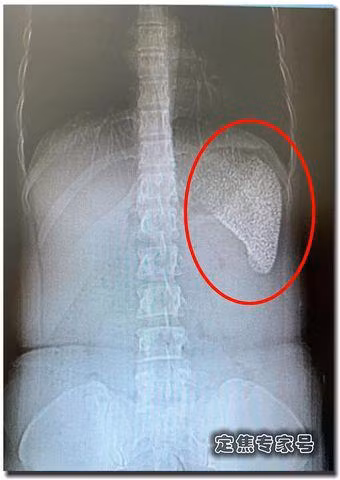

Phim chụp CT của Hà Lệ Lệ.

Nhìn phim chụp CT của Hà Lệ Lệ, màu trắng trong phim chụp chính là lá lách của cô. Hình ảnh chụp CT của Lệ Lệ cho thấy lá lách có những lỗ rỗng màu đen, được bao phủ hoàn toàn bằng màu trắng, điều đó có nghĩa là lá lách của cô đã thực sự đã bị “hỏng”, bên trong đều là những vết vôi hóa, giống như là một viên gạch rỗ.

Vào giữa tháng 5, Hà Lệ Lệ tìm đến bác sĩ Lý Bỉnh Lộ, giáo sư khoa phẫu thuật cơ bản của Bệnh viện Dung Hợp Bắc Kinh. Sau khi xem phim chụp CT của Hà Lệ Lệ, bác sĩ Lý Bỉnh Lộ cũng là lần đầu tiên nhìn thấy trường hợp này. Nó không phải là khối u cũng không phải là nhiễm trùng, cũng không phải là hoại tử.